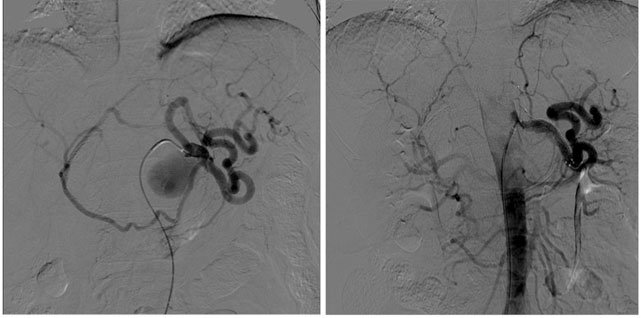

In questo contesto intendiamo degli interventi con un catetere che si possono effettuare attraverso un accesso percutaneo (senza tagli chirurgici) all’interno del vaso sanguigno (trans-luminali). Una possibilità di intervento di questo tipo è l’angioplastica percutanea trans-luminale (PTA), con la quale si può dilatare un vaso sanguigno ristretto, o riaprirlo se occluso, senza operazione. Si esegue mediante un sottile tubo di plastica di 1–2 mm di diametro, munito all’estremità di un palloncino gonfiabile (catetere a palloncino). Con questo palloncino si possono dilatare dall’interno, in modo indolore, tratti ristretti o occlusi delle arterie. Perciò questo procedimento è chiamato anche «dilatazione con il palloncino». Lo si effettua in anestesia locale, senza narcosi. Dato che la posizione esatta del catetere a palloncino dev’essere controllata con un apparecchio radiologico, la PTA si fa nella sala di radiologia.

Se il risultato della dilatazione col palloncino è insufficiente si può procedere all’applicazione di uno stent. Uno stent è un sostegno o un’armatura che mantiene aperta l’arteria dilatata (figura 2) qualora la sola dilatazione col palloncino è insufficiente. Gli stent si possono inserire in quasi tutte le arterie. Si introducono attraverso la stessa apertura praticata sulla cute ed utilizzata per far passare il catetere a palloncino, senza che il paziente se ne accorga.

Procedure minimamente invasive che utilizzano palloncini o stent medicati o non medicati

I palloncini e gli stent medicati usano una piccola quantità di farmaco per mantenere l’arteria aperta più a lungo

Una quantità molto piccola di un farmaco denominato paclitaxel viene posta su palloncini o stent; il farmaco si trasferisce quindi alla parete dell’arteria durante la procedura

Questo farmaco aiuta a mantenere le arterie aperte più a lungo rispetto a palloncini o stent non medicati